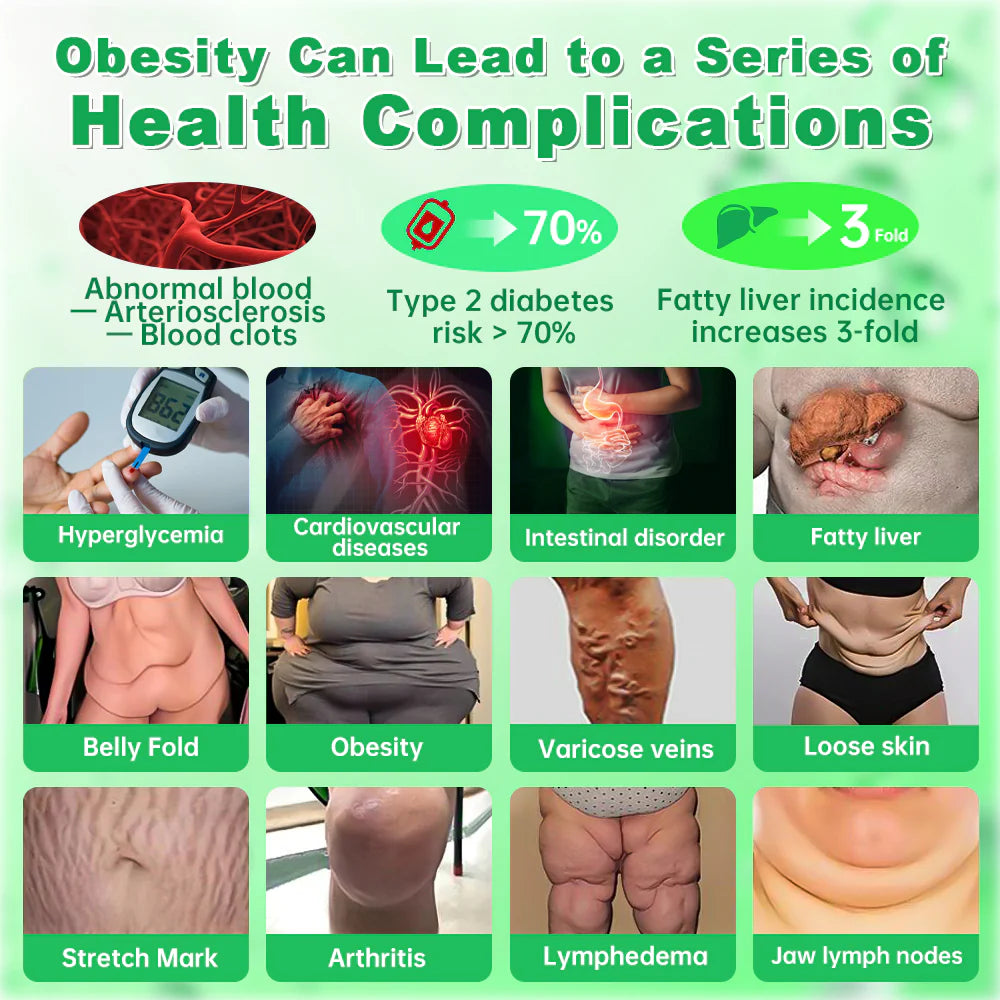

Are you troubled by health problems caused by obesity?

Health problems caused by obesity

The health problems caused by obesity are gradually taking away your vitality.

Cardiovascular Disease

Obesity increases the risk of high blood pressure, high cholesterol, and atherosclerosis, which can lead to heart disease, myocardial infarction, and stroke.

Respiratory Disorders

Obese individuals are more likely to experience sleep apnea, asthma, and impaired respiratory function.

Type 2 Diabetes

Excess fat, especially abdominal fat, can lead to insulin resistance, increasing the risk of developing diabetes.

Certain Cancers

Obesity increases the risk of colorectal cancer, breast cancer, endometrial cancer, and pancreatic cancer, which may be related to inflammation and changes in hormone levels.